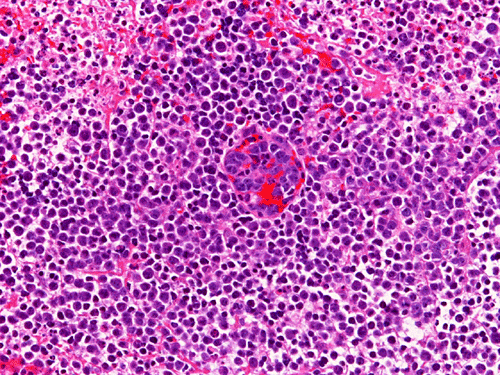

The material for permanent sections is largely semi-liquid in consistency. There are only very few fragments of cerebellar tissue that are infiltrated by the tumor. The bulk of the diagnostic material are solid sheets of neoplastic cells (Panel G). The cytologic features are similar to what we have observed in the cytologic preparation  (Panel H). In essence, the tumor is composed of solid sheets of large polygonal and rather monotonous atypical cells with a thin rim of cytoplasm and molding which lead to a mosaic pattern. These features are consistent with lymphoma. On immunohistochemistry, practically all the neoplastic cells are positive for leukocyte common antigen (LCA) (Panel I), CD20 (Panel J) and many of them are positive for CD79a (Panel K). Only reactive T-cells but not the large, atypical cells are positive for CD3 (Panel L). The neoplastic cells are essentially negative for Bcl-6 (Panel M) but some of them are positive for Bcl-2 (Panel N). The large atypical cells are negative for kappa and lambda light chains on immunohistochemistry. There is no immunoreactivity in the neoplastic cells for cytokeratin (AE1/AE3), S100, pan-melanoma marker (Mart-1, tryptase, and HMB-45).

Similar to the systemic counterparts, diffuse large-B cell lymphomas of the CNS are characterized by large, pleomorphic lympyoid cells. Histologically, however, PCNSL shows the unique angiocentric infiltrating pattern, which is more prominent at the edge of the lesion. The tumor cells dissect and expand the perivascular network in a concentric manner which is best demonstrated by reticulin stain

[click here to see a picture]. Systemic DLBCL does not show this particular pattern of growth. The tumor infiltrates the brain parenchyma between blood vessels as small clusters and individual cells. Confluent areas of tumor may show necrosis, with residual viable tumor cells being found mostly around blood vessels. The boundary of the tumor may be relatively discrete, but it is more common for perivascular cuffs and single infiltrating lymphoma cells to be found at some distance from the tumor mass, extending far away from radiographically evident tumor margins. The malignant lymphocytes lack a cohesive appearance, do not form glands or other structures. The nuclei vary from round to indented or cleaved, and prominent nucleoli can be noted. The cells have only a small amount of basophilic cytoplasm. Variable numbers of mitotic figures and apoptotic cells are seen.